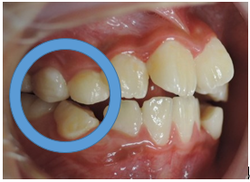

さて、この様な歯並びの方はかなり見受けられると思われます。

→

当矯正歯科医院では、咬合バランスを改善する為には、

顎骨の拡大だけでは不十分と考えています。

その為、かみ合わせの高さなどを立体的に改善していく事を心がけて日々治療しています。

今回も治療には、独自の方法とビムラー装置・t4k等を利用して改善しました。